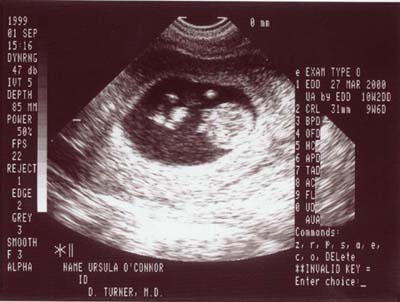

Erin & Ursula would like to announce

Junior/Juniorette is on his/her way...

Ultrasounds taken at 10 weeks